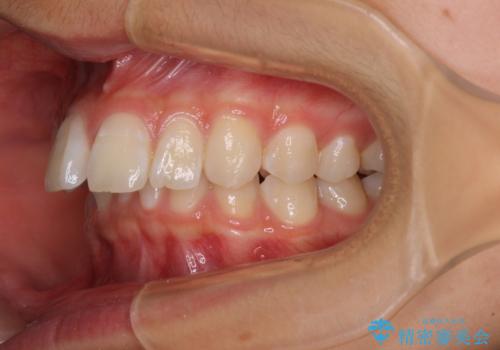

深い咬み合わせで前方に煽られた前歯 高校生のインビザライン矯正治療

奥歯の咬み合わせと深い咬み合わせを改善した後、隙間などをインビザラインで整えることとしました。

インビザラインをしっかりと装着したことはもちろん、高校生は歯の動きが早いため、非常に短期間で治療を終えることができました。